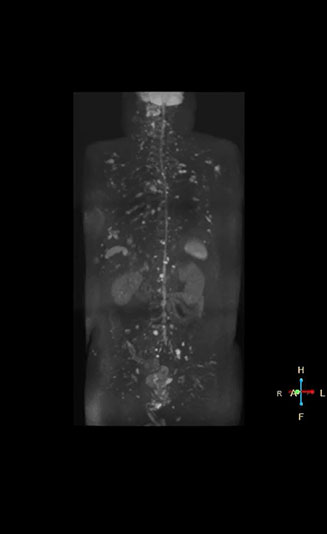

Coronal DWIBS is faster and improves image quality

“Switching to coronal DWIBS – rather than axial – further shortens scan time,” says Mr. Naka. “Important is that a dS SENSE factor of 5 shortens exam time while high image quality can be maintained, thanks to Ingenia’s dStream architecture.” He adds that the coronal orientation also avoids artifacts that are specific to combining axial images.

“When we use a coronal DWIBS acquisition, we can perform a full whole body examination, including other required sequences, within 30 minutes,” he says.

“This is considerably faster than the previously used exam with axial whole body DWI, which took more than 45 minutes,” he notes. “A shorter exam is more patient-friendly and allows us to also use it on patients in poor health who would have difficulty tolerating a long exam. Limiting the exam time is also helpful for scheduling, because it fits in a normal single exam timeslot.”